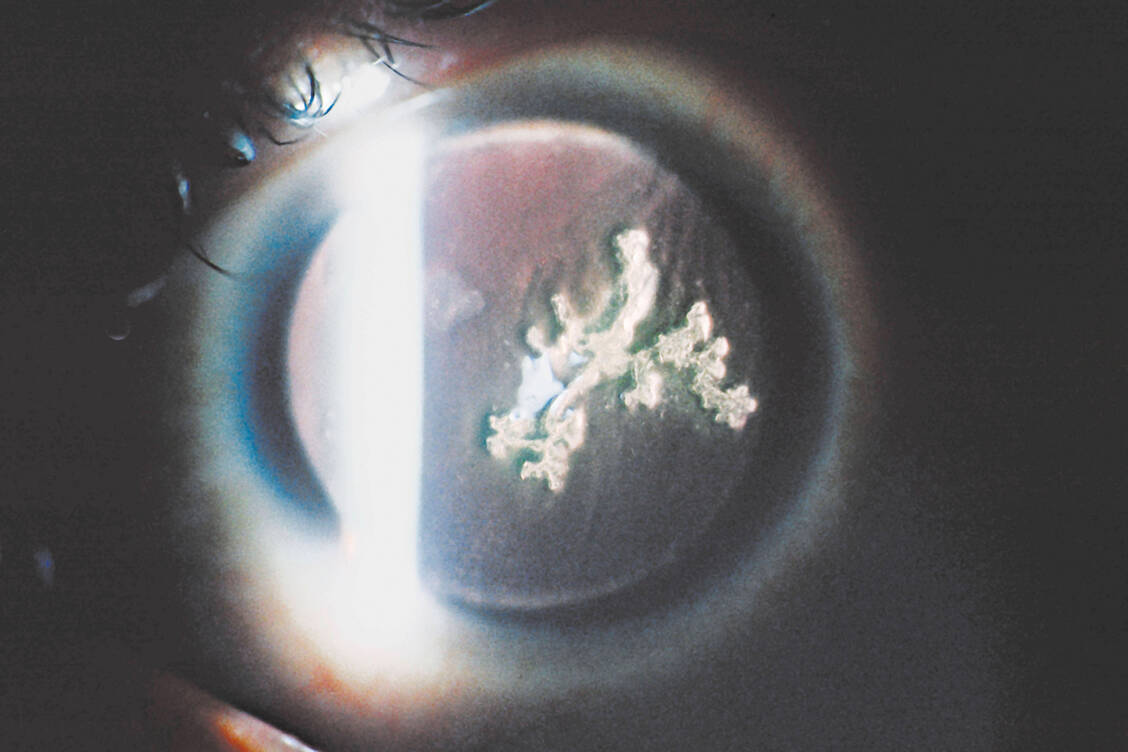

HSV-Keratitis

Wie ein Herpes im Auge behandelt wird

Schmerzen, Brennen und Fremdkörpergefühl – das sind typische Symptome einer Herpes-simplex-Infektion des Auges. In den meisten Fällen infizieren die Viren die inneren Bereiche des Auges wie die Binde- und Hornhaut, was eine schnelle Diagnose deutlich erschwert. Bei Verdacht sollten Betroffene sofort einen Augenarzt aufsuchen, damit eine antivirale Therapie begonnen werden kann.

Eine Infektion mit Herpes-simplex-Viren (HSV), insbesondere HSV1, wird in den meisten Fällen als Lippenherpes deutlich. Seltener und mit einer Inzidenz von rund 6 bis 18 Personen pro 100.000 können diese Viren auch die Augen befallen und dort Strukturen der Hornhaut infizieren.

Die sogenannte HSV-Keratitis ist eine entzündliche Erkrankung, von der alle Altersgruppen betroffen sein können. Übertragen als Schmierinfektion nach Kontakt mit einem Herpesbläschen einer anderen Person oder einer infizierten Oberfläche können Symptome am Auge, der Bindehaut und der Hornhaut entstehen.

Kunden mit einer möglichen HSV-Keratitis beschreiben im Beratungsgespräch Symptome wie einen gesteigerten Tränenfluss, ein Fremdkörpergefühl, Schmerzen und Rötungen am betroffenen Auge sowie eine auffällige Lichtempfindlichkeit. Ergänzend können sich Bläschen außerhalb des Auges bilden, die im Verlauf einem Lippenherpes ähneln. In den meisten Fällen sind allerdings ausschließlich die Bereiche im Auge infiziert.